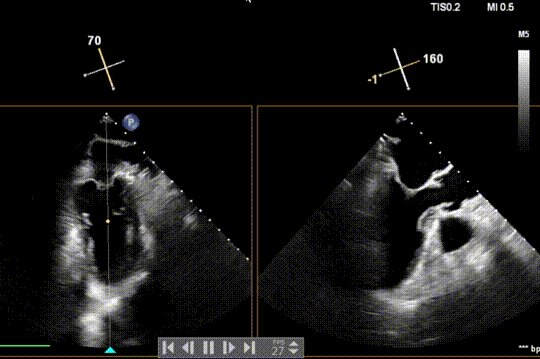

患者为原发性二尖瓣反流(DMR),收缩期可见二尖瓣反流信号,反流位于 2 偏 3 区,基线期二尖瓣反流程度4+。

前叶长度 15.7mm,后叶长度 12.7mm,后叶脱垂宽度13.9mm,脱垂高度4.76mm, 瓣环直径37.1mm,VC:4*7mm, MVA约4cm² 。瓣叶质地较差,腱索断裂、后瓣叶脱垂。

术前超声